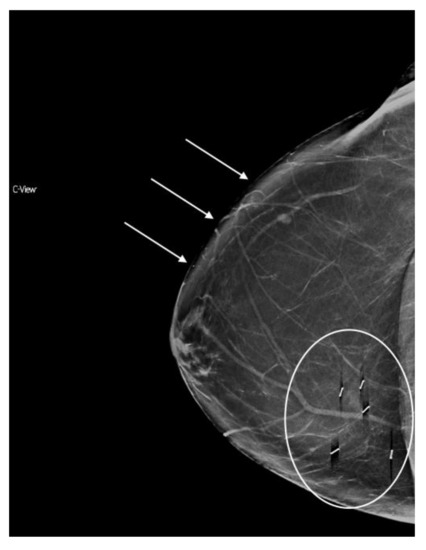

Of note, with synthesized mammography, the recall rate (RR) of women with dense breasts has been shown to approach that of 2D FFDM for women with non-dense breasts (RR dense breasts with s2D+DBT 7.11 vs. RR non-dense breasts with 2D FFDM 7.34%) [31]. Additional studies to subanalyze the effect of breast density on performance outcomes with synthesized mammography are needed. (Figure 1).

Figure 1.

The four categories of breast density on conventional 2D FFDM and synthesized mammography. (a) Predominantly fatty breast 2D FFDM (b) Predominantly fatty breast s2D FFDM (c) Scattered fibroglandular breast 2D FFDM (d) Scattered fibroglandular breast s2D (e) Heterogeneously dense breast 2D FFDM (f) Heterogeneously dense breast s2D (g) Extremely dense breast 2D FFDM (h) Extremely dense breast s2D.